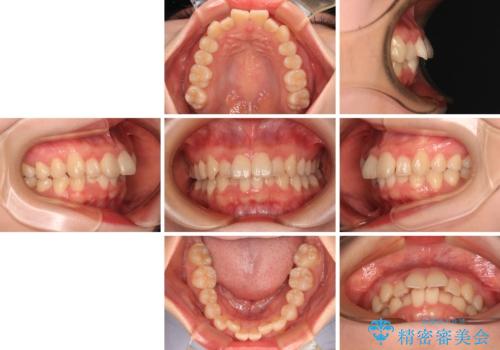

飛び出した前歯を引っ込める ワイヤー装置の非抜歯矯正

- 上下前歯のデコボコを気にして来院された患者様です。

マウスピースでもワイヤー装置でも対応可能でしたが、右側の咬み合わせが上顎がやや前方に位置していることから、補助装置を使用することが推奨されました。

自己管理の煩わしさを気にして、補助装置併用によるワイヤー装置での矯正治療を行うこととしました。

右上と左下の第一大臼歯2本が周辺の歯と比べて位置がずれていたため、ゴムかけやワイヤーに曲げを入れることで移動を試みましたが、どうよら癒着をしており、移動困難と判断されました。

見た目や咬み合わせに違和感がないとのことで、癒着歯の無理な移動は試みずに治療を終えることとしました。